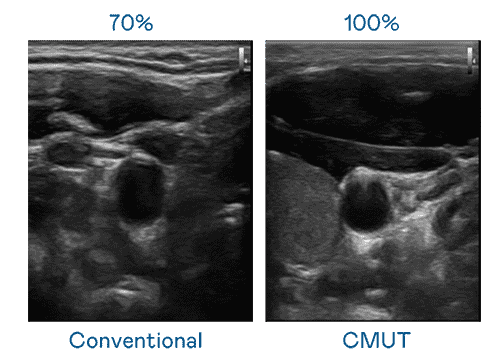

CMUT 技术是一种用电容式微机电元件来产生超音波讯号的技术。。与传统 PZT 压电式技术相比,,,CMUT 频宽增加 30%,,更宽频的超音波讯号让影像解析度大幅提升,,,,是实现高影像品质医疗超音波扫描、、、促进精准医疗发展的关键技术。。

大频宽带来超清晰影像

超音波影像的解析度高低,,,,首先取决于探头能发出的讯号频宽。。杏悦2 CMUT 可提供高清晰的超音波讯号,,提供高频宽、、、、高灵敏度、、、、影像纹理细节更高的超音波影像,,,,协助医护人员缩短影像判读时间及利用精准的医疗影像进行诊断。。。